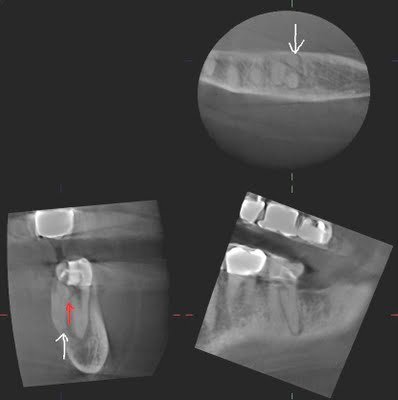

This patient came to SSE for emergency treatment. #18 DX: Necrotic pulp w/ Symptomatic Apical Periodontitis. RCT initiated. 3 canals located, however a 4th distal canal is not found. 2 distal roots are apparent the pre-op film. The ML, MB and a distal canal are located. The distal is opened looking for the 4th canal. After 20-30 minutes of searching for 4th canal, the patient is re-appointed for 2 step treatment.

Upon return for second visit, the symptoms of SAP have not completely resolved. Slight vestibular swelling noted. We decided at that point to take a CBCT to help us located the 4th canal.

The CBCT clearly shows us that a perforation has been created (red arrow), and the additional canal/root is lingual to the DB canal. A sagittal view, provided only by CBCT, can provide information that is not available by conventional radiography.